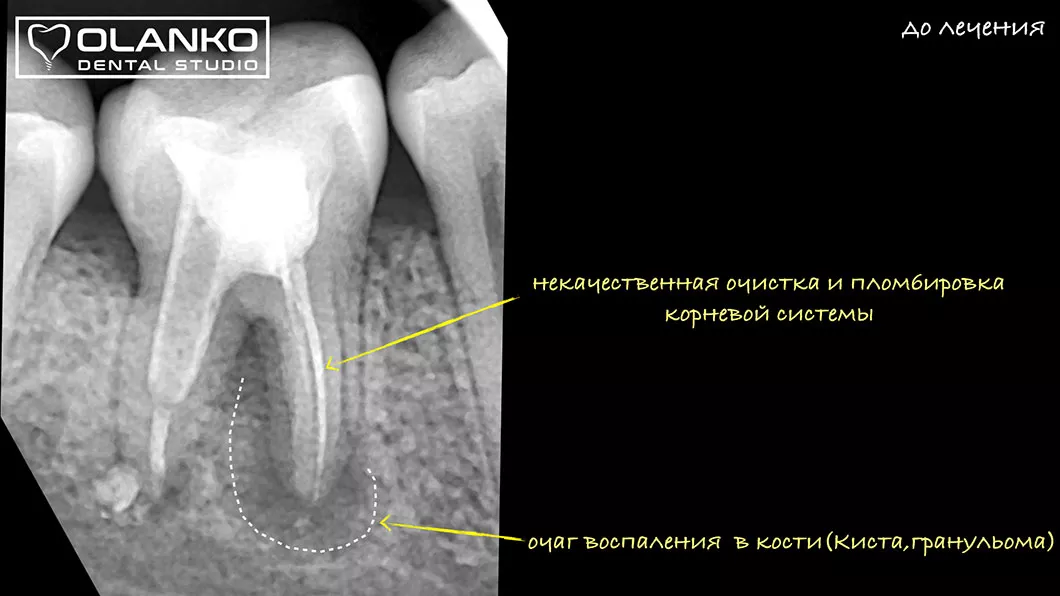

На примере перелечивания корневых каналов верхнего жевательного зуба

Лечение корневых каналов зуба с использованием микроскопа, на сегодняшний день, является золотым стандартом мировой стоматологической практики. Сложная система корневых каналов в зубе имеет очень малый диаметр и индивидуальную анатомию, поэтому врач, работающий без увеличения, не может качественно очистить и найти все корневые каналы на ощупь.

Мы имеем огромный клинический опыт лечения зубов со сложной анатомией (искривлёнными, склерозированными каналами), а также повторного перелечивания каналов с кистами, гранулемами, сломанными инструментами, с последующими отличными результатами заживления очагов хронического воспаления.